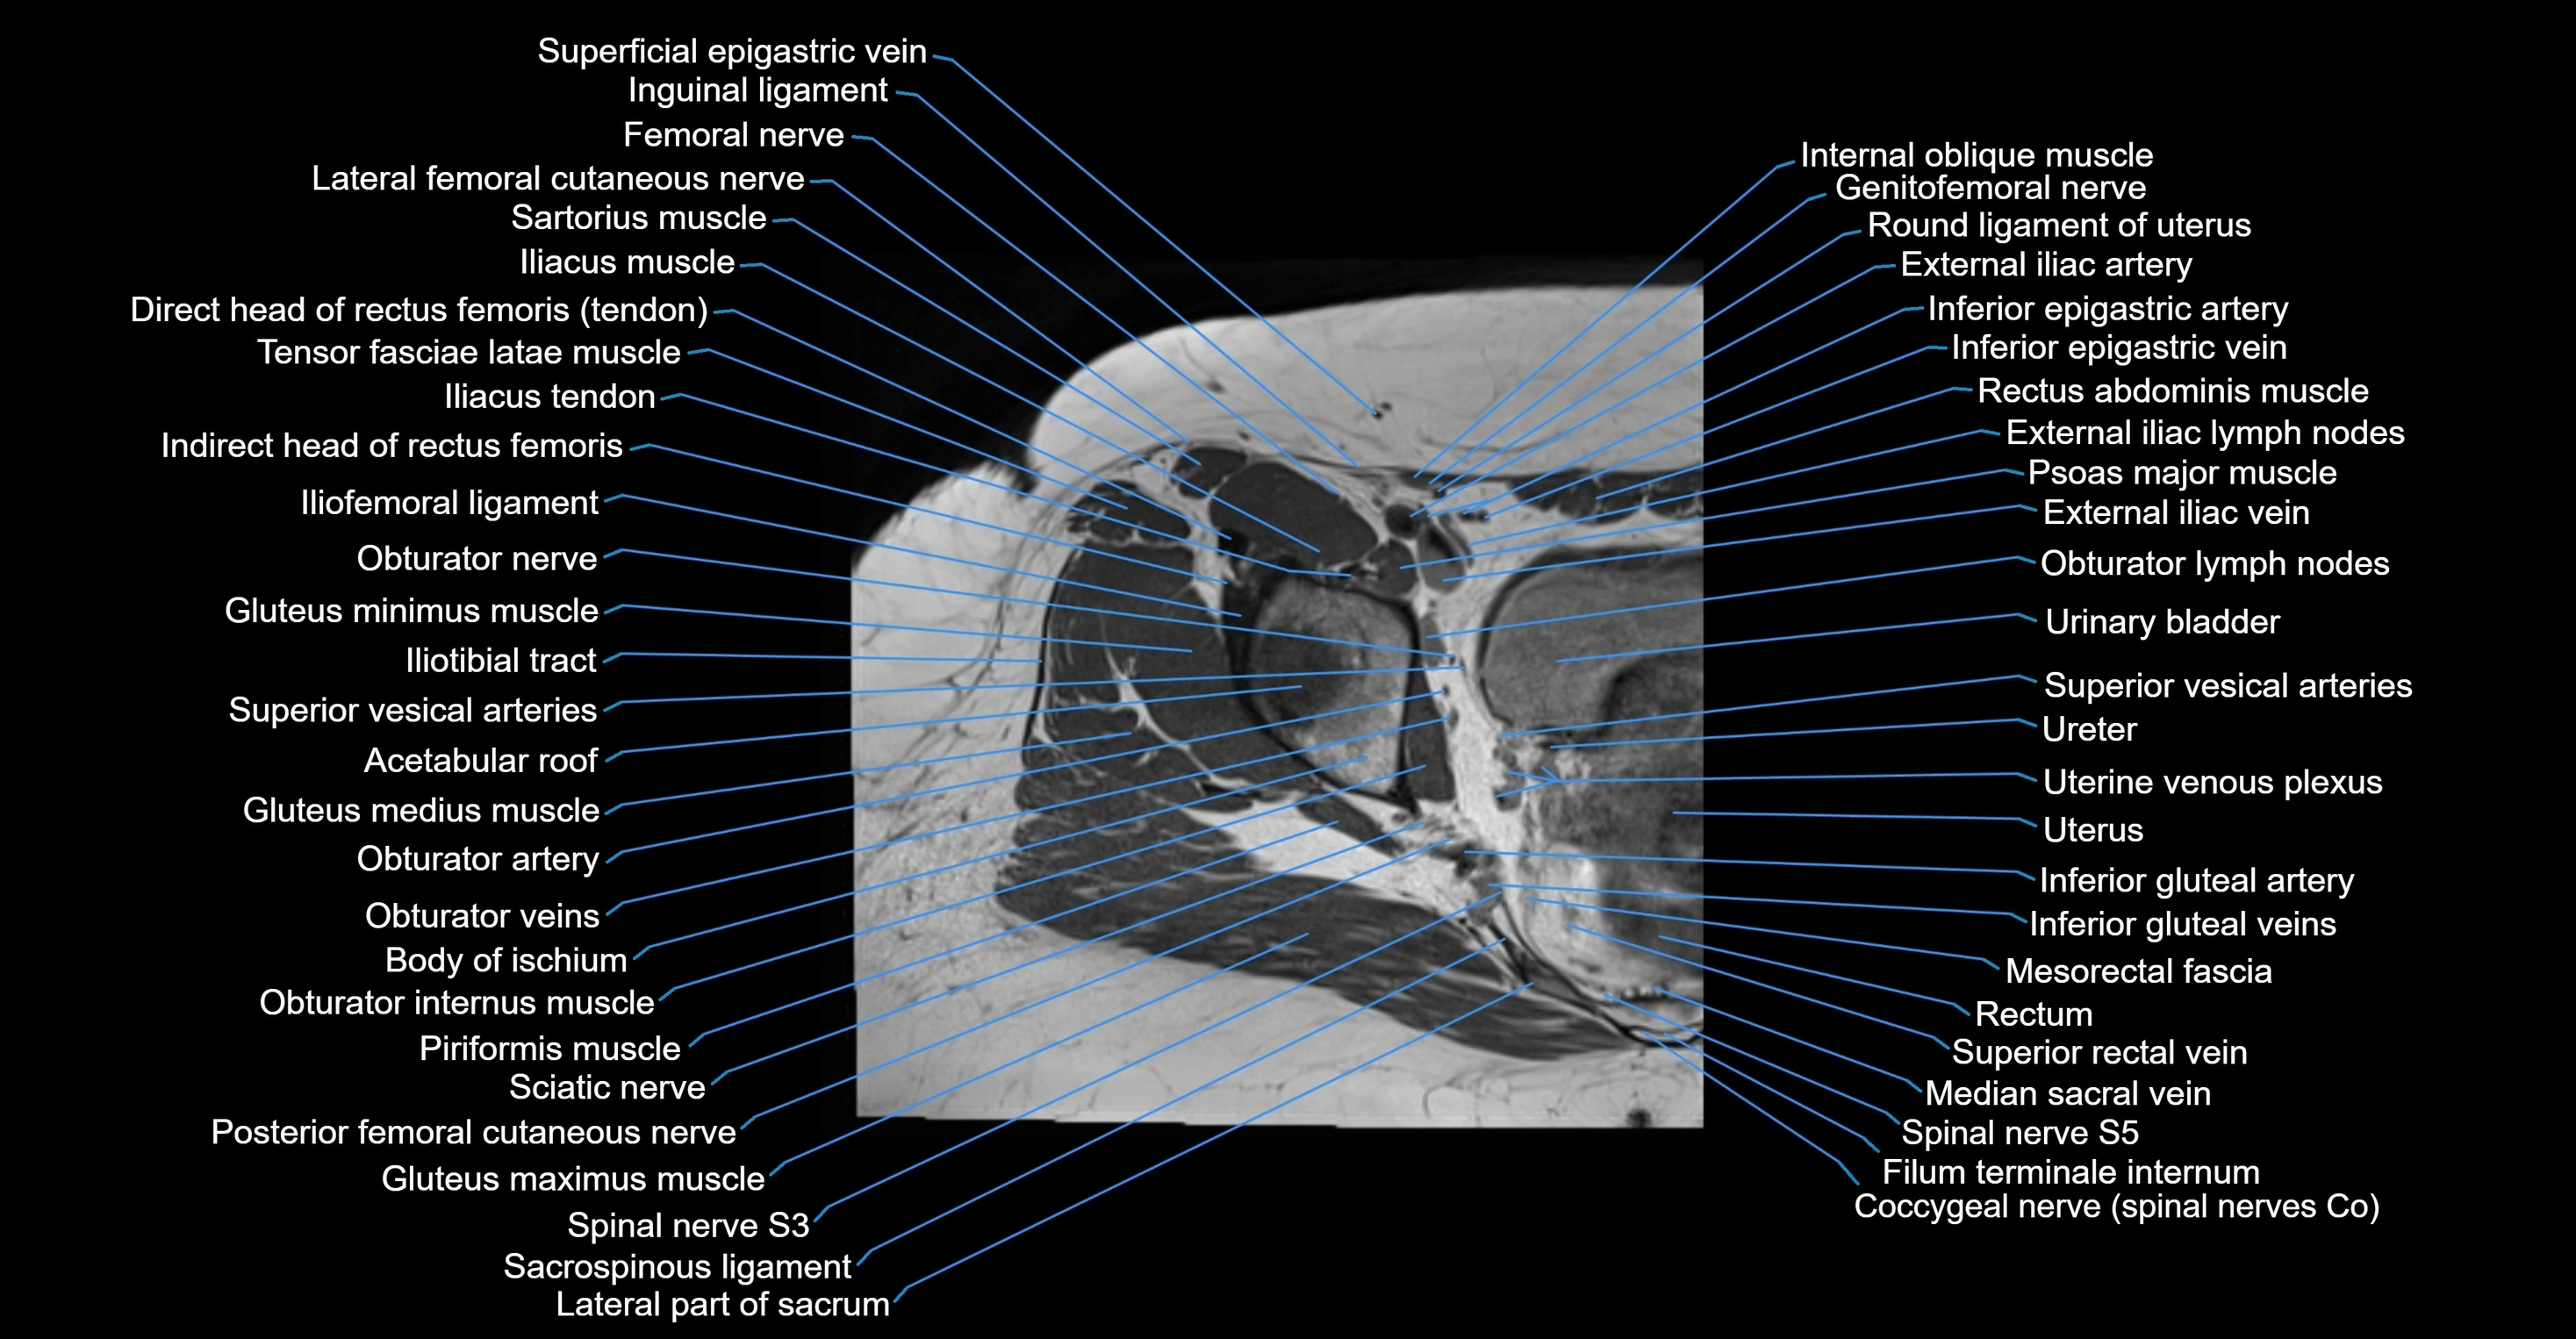

- External iliac artery

- External iliac vein

- Femoral nerve

- Filum terminale internum

- Genitofemoral nerve

- Gluteus maximus muscle

- Gluteus medius muscle

- Gluteus minimus muscle

- Iliococcygeus muscle

- Iliotibial tract

- Inferior epigastric artery

- Inferior epigastric veins

- Inferior gluteal artery

- Inferior gluteal vein

- Inguinal ligament

- Inguinal lymph nodes

- Lateral femoral cutaneous nerve

- Levator ani muscle

- Median sacral vein

- Mesorectal fascia

- Obturator internus muscle

- Obturator nerve

- Obturator veins

- Posterior femoral cutaneous nerve

- Psoas major muscle

- Pubococcygeus muscle

- Pyramidal muscle (pyramidalis muscle)

- Rectum

- Round ligament of uterus

- Sacral plexus

- Sacrospinous ligament

- Sartorius muscle

- Spinal nerve L5

- Spinal nerve S1

- Spinal nerve S2

- Spinal nerve S3

- Spinal nerve S4

- Spinal nerve S5

- Superior rectal vein

- Superior vesical artery

- Tensor fasciae latae muscle

- Urinary bladder

- Uterine venous plexus

- Uterus